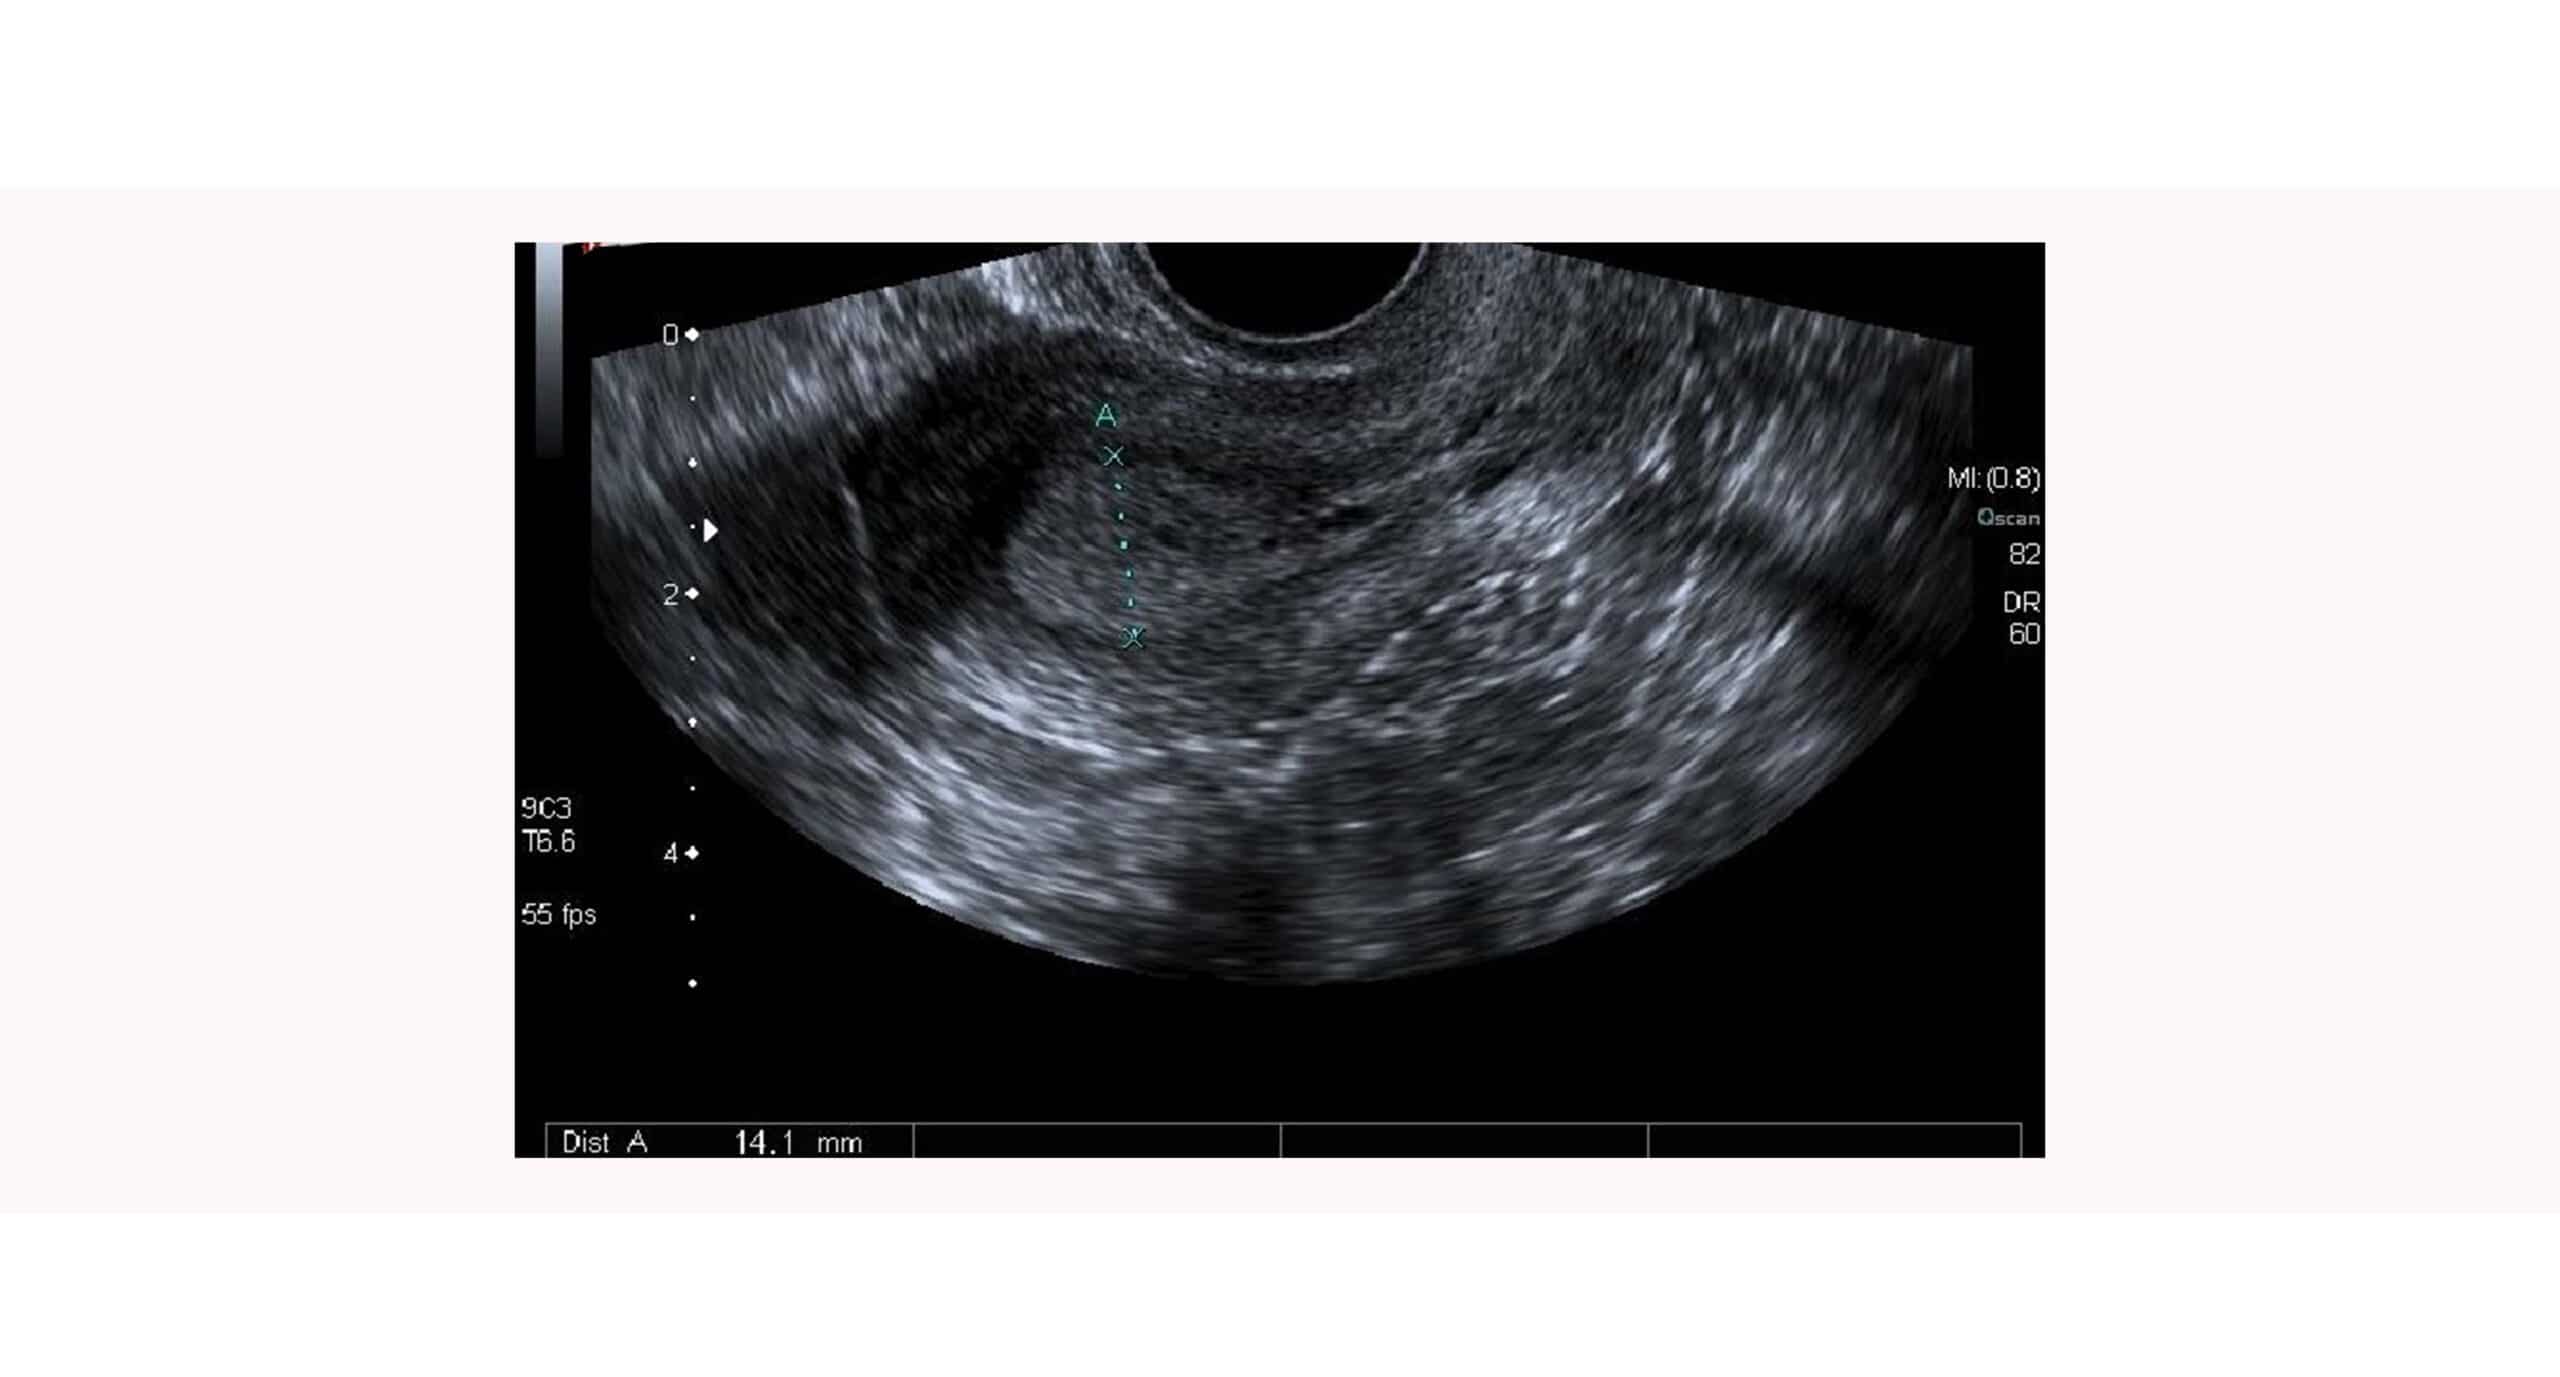

El segundo invitado: el endometrio. Es el tejido que recubre la cara interna del útero. Al contrario de lo que se pensaba hace algunos años, no es un tejido estéril si no rico en microorganismos que le dan propiedades especiales necesarias para este proceso. Para que el embrión sea capaz de invadir el endometrio es imprescindible que el proceso se lleve a cabo durante la ventana de implantación. Ésta es un periodo de aproximadamente cuatro días en el que los cambios a nivel del endometrio favorecen la implantación del embrión.

Tal y como hemos comentado, la implantación embrionaria es el proceso en el que el embrión se implanta en el endometrio, se adhiere a él. Para ello, es muy importante que el endometrio pase de un estado no receptivo a receptivo bajo la influencia hormonal y que exista una sincronía entre embrión y endometrio.

En la mayoría de mujeres, la ventana de implantación comprende desde el día 20 hasta el día 24 del ciclo menstrual. En este momento, si ha habido fecundación, el blastocisto tendrá unos 6 o 7 días y estará preparado para implantar.

Las condiciones receptivas endometriales se alcanzan en torno a 6-7 días después de la ovulación, momento en el que el endometrio está en su fase de secreción máxima, debido al estímulo de la progesterona.